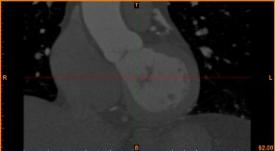

首先通过病人的心脏冠脉造影CT数据,获取病人的心脏冠脉三维模型。

病人的冠脉造影CT数据 提取出的冠脉三维数据